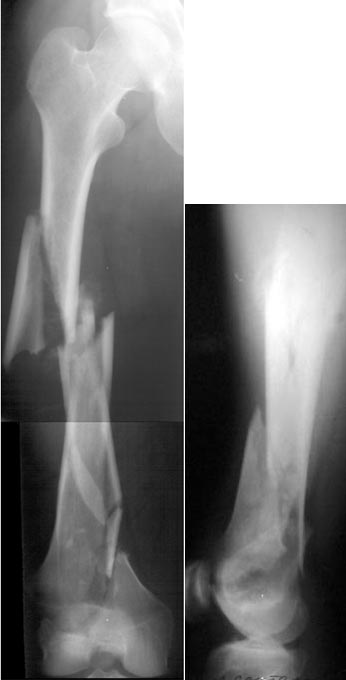

of course the only radiograms both the view of the femur (AP and LL) are not enough in order to assess the condilar ones.

Are you sure you want to operate this patient?

He survived 1 month on traction, the most difficult part of it!

The best healing is anticipated if the fracture site is not opened (virtually the whole thigh in your tough case!).

ExFix could be good biologically, what kind of frame would you use?

IM nailing, may be retrograde (for sure not

antegrade), either way it would be very-very

difficult.

I am sure that you assessed adequately the condylar fractures, they may need fixation (eg. percutaneous screws).

I tried to think of LISS, but it would be difficult to perform after a month (no fracture hematoma but there is fibrosus callus formation). And even the longest LISS would be short here, not to mention the very small distal piece.